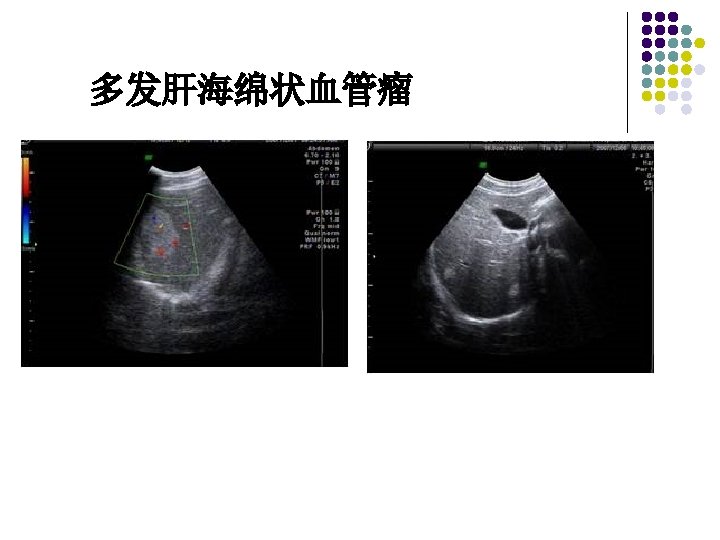

Hepatic hemangioma / Cavernous hemangioma of liver l l CH of the liver is composed of blood-filled fairly large or tortuous vascular cavities divided by thin, often incomplete, fibrous septa and lined by a single layer of flat endothelium The blood flow in the vascular spaces is slow and nondirectional which is predisposed to thrombosis

Ultrasonic features of Hepatic hemangioma l l l Uniformly hyperechoic mass(60 -70%) Inhomogeneous hypoechoic mass (up to 40%) Homogeneous(58 -73%) /heterogeneous May show acoustic enhancement(37 -77%) Unchanged in size/appearance(82)on 1 -to-6 year follow-up No Doppler signals/signals with peak velocity of <50 cm/cm